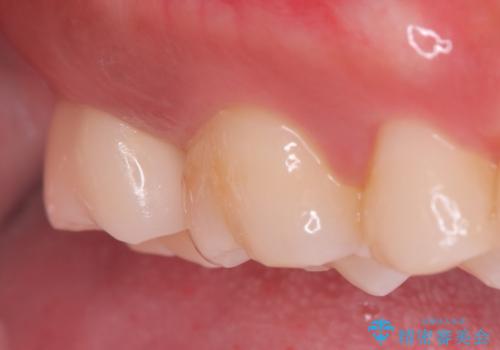

- 海外に転居する前に治療を完了させたいと来院された患者様です。

根管治療からセラミッククラウンまで来院回数は5回で治療を完了することができました。

治療前は遠心のポケットが7mmほどありましたが、治療後には3mmに改善しています。